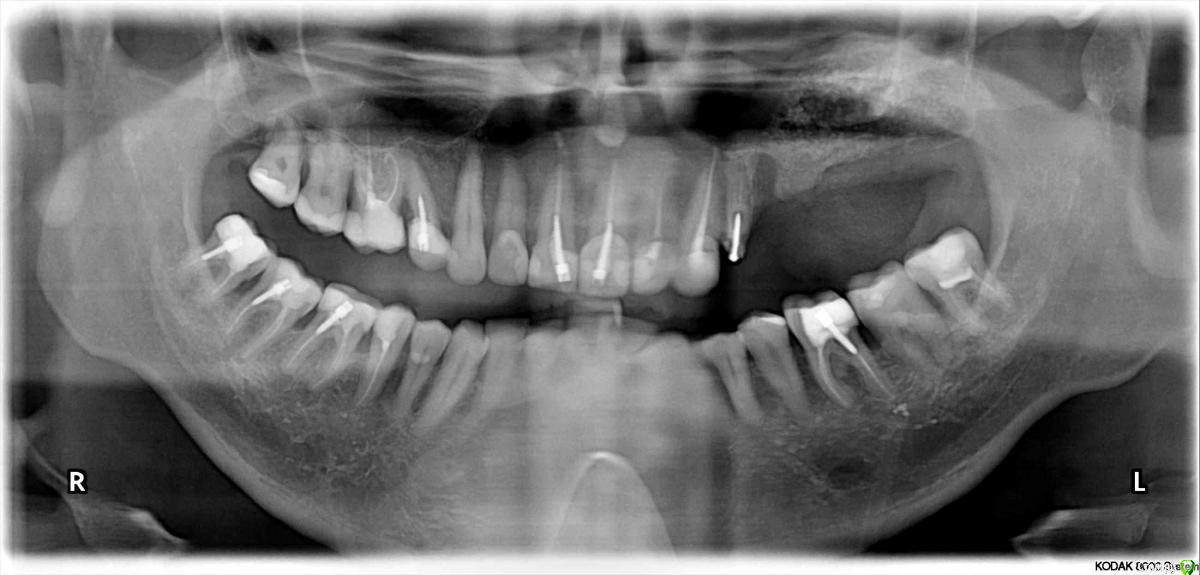

red_butler Опубликовано 16 апреля, 2015 Поделиться Опубликовано 16 апреля, 2015 Только что закончил синуслифтинг. В самом конце стал фиксировать мембрану пинами, ручка соскользнула. Под трясываясь проверяю и отправляю пациента на ОПГ. В общем слизистая поднялась в два раза больше чем планировал. Ушел весь запас графта какой был. 1,5 кубика остеосса, кубик биоосса и кубик остеона. Сегодня выпью за здоровье синуса. 1 Ссылка на комментарий

Magomed Опубликовано 16 апреля, 2015 Поделиться Опубликовано 16 апреля, 2015 Только что закончил синуслифтинг. В самом конце стал фиксировать мембрану пинами, ручка соскользнула. Под трясываясь проверяю и отправляю пациента на ОПГ. В общем слизистая поднялась в два раза больше чем планировал. Ушел весь запас графта какой был. 1,5 кубика остеосса, кубик биоосса и кубик остеона. Сегодня выпью за здоровье синуса.пинов не вижу. А зачем так подняли? Ссылка на комментарий

Acidrocker Опубликовано 16 апреля, 2015 Поделиться Опубликовано 16 апреля, 2015 Был похожий синус у меня, пазуха клинически здорова. 2 Ссылка на комментарий